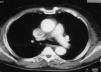

Fig. 1.

Fig. 2.

Fig. 3.

Fig. 4.